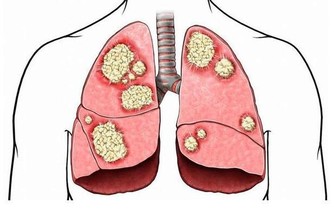

6、可能患癌。手腳冰涼的人容易得癌?這讓很多女性感到震驚,對他們來說,一到冬天老覺得手腳不暖和幾乎已經成為一種「常態」,可是否這樣就真的會被癌症纏上呢?

答案是會!

如果常年手腳冰涼,平時經常覺得疲勞怕冷、打不起精神、唇色較淡、性慾減退,男性經常遺精,女性白帶清稀,則需要提高警惕。

因為這類人就屬於寒性體質,也就是陽虛體質。

穿再厚都覺得冷